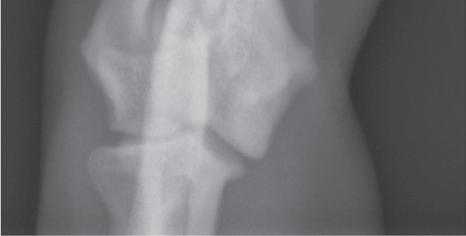

the top and the distal aspect at the bottom. These can all be considered sagittal-plane radiographs. There is no convention directing whether the medial or lateral side of the extremity should be on the examiner’s left (Figure 1-5). This orientation is correct regardless of whether the left or right limb has been imaged.

Figure 1-5. Correct orientation of a sagittal-plane radiograph of an extremity. A caudocranial view of a humerus is shown here. There is no convention regarding whether the lateral side of the limb is placed on the examiner’s right (A) or left (B). However, it is probably more common to orient medial and lateral relative to the patient. As such, a left limb would be oriented as in Figure 1-5A, and a right limb would be oriented as in Figure 1-5B.